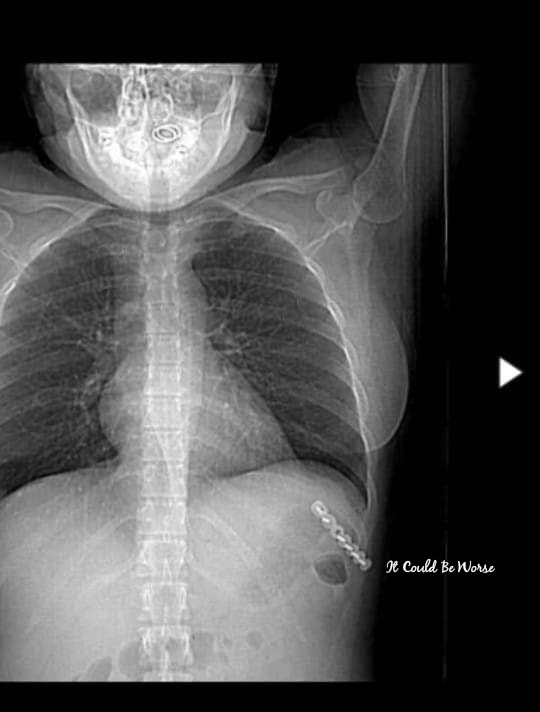

The positive is that I finally got imaging of the rib plate that had been placed in May for my Slipping Rib Syndrome at ribs 9-10. I was excited just to see what it looked like, to find out the details that I hadn’t been able to get with my online medical file – I hadn’t had imaging since before the procedure.

On Friday, I woke up coughing and with severe rib pain again, so I called my doctor to be seen. I wanted to try to avoid the emergency room and that chaos, so I scheduled to see her in an hour – I got lucky and she could see me that quickly. I didn’t even get out of pajamas for that appointment, and she ordered up an x-ray for my thoracic area.

She told me to start using my steroid inhaler again and try to rest. She didn’t see anything in the x-rays, granted, they never see anything – I know this because I lived with my fracture for a year, with multiple scans and imaging tests that all showed nothing.